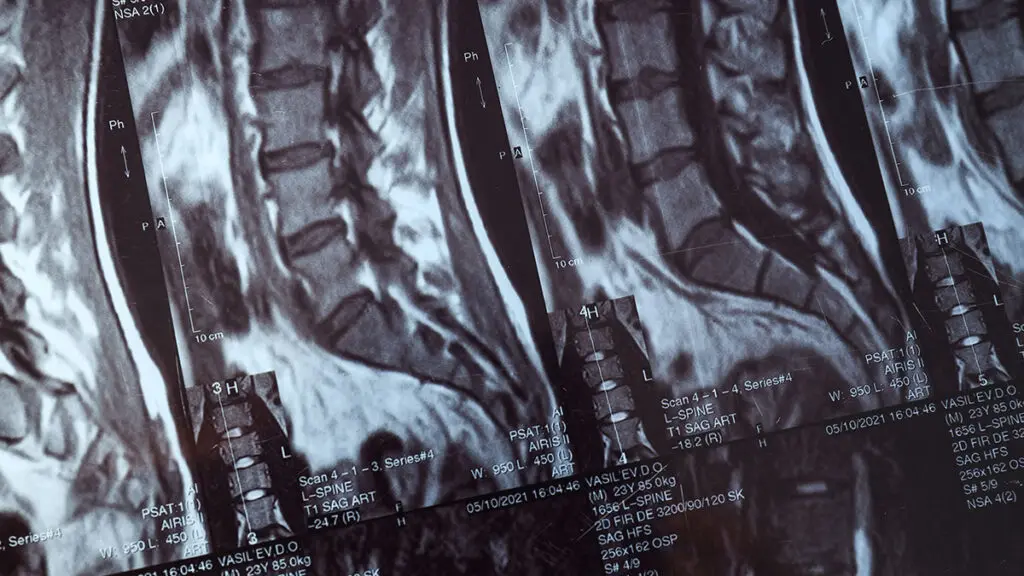

Tecnologie diagnostiche per la cura delle patologie spinali – Global Spine Solutions Roma

Strumentazione diagnostica e terapeutica di ultima generazione